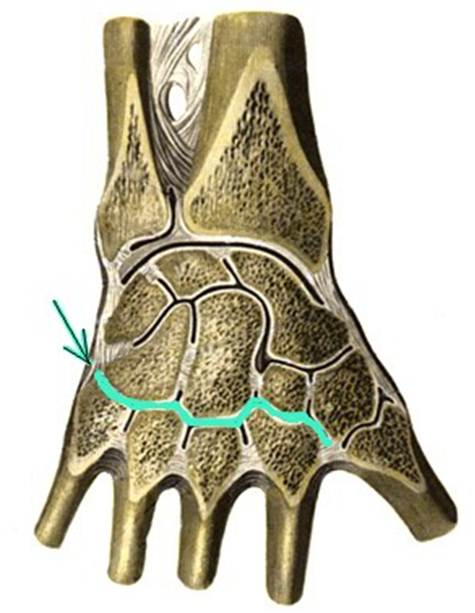

S: Стрелка указывает на art. Mediocarpalis

S: Стрелка указывает на art. Carpometacarpalis

S: Стрелка указывает на art. capri

S: Стрелка указывает на discus articularis

S: Стрелка указывает на art. Metacarpophalangea

S: Стрелка указывает на art. Interphalangea manus

S: Стрелка указывает на art. Interphalangea manus

S: Стрелка указывает на art. Interphalangea manus